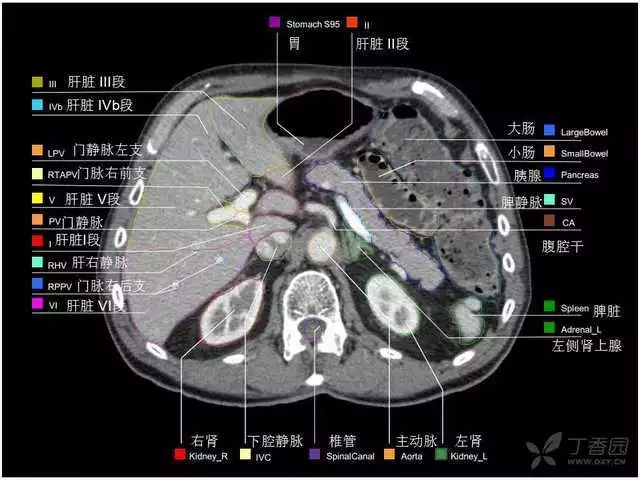

腹部肝脏高清CT断层的图谱

全腹部高清CT图谱,淋巴结彩色图谱,血管解剖图谱大汇总!